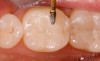

Figure 2